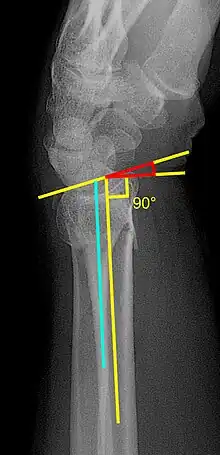

Fracture with a dorsal tilt: Dorsal is left, and volar is right in the image.

• Volar or dorsal tilt - A line is drawn joining the most distal ends of the volar and dorsal side of the radius. Another line perpendicular to the longitudinal axis of the radius is drawn. The angle between the two lines is the angle of volar or dorsal tilt of the wrist. Measurement of volar or dorsal tilt should be made in true lateral view of the wrist because pronation of the forearm reduces the volar tilt and supination increases it. When dorsal tilt is more than 11 degrees, it is associated with loss of grip strength and loss of wrist flexion.[5]

• Radial inclination - It is the angle between a line drawn from the radial styloid to the medial end of the articular surface of the radius and a line drawn perpendicular to the long axis of the radius. Loss of radial inclination is associated with loss of grip strength.[5]

• Radial length - It is the vertical distance in millimetres between a line tangential to the articular surface of the ulna and a tangential line drawn at the most distal point of radius (radial styloid). Shortening of radial length more than 4mm is associated with wrist pain.[5]